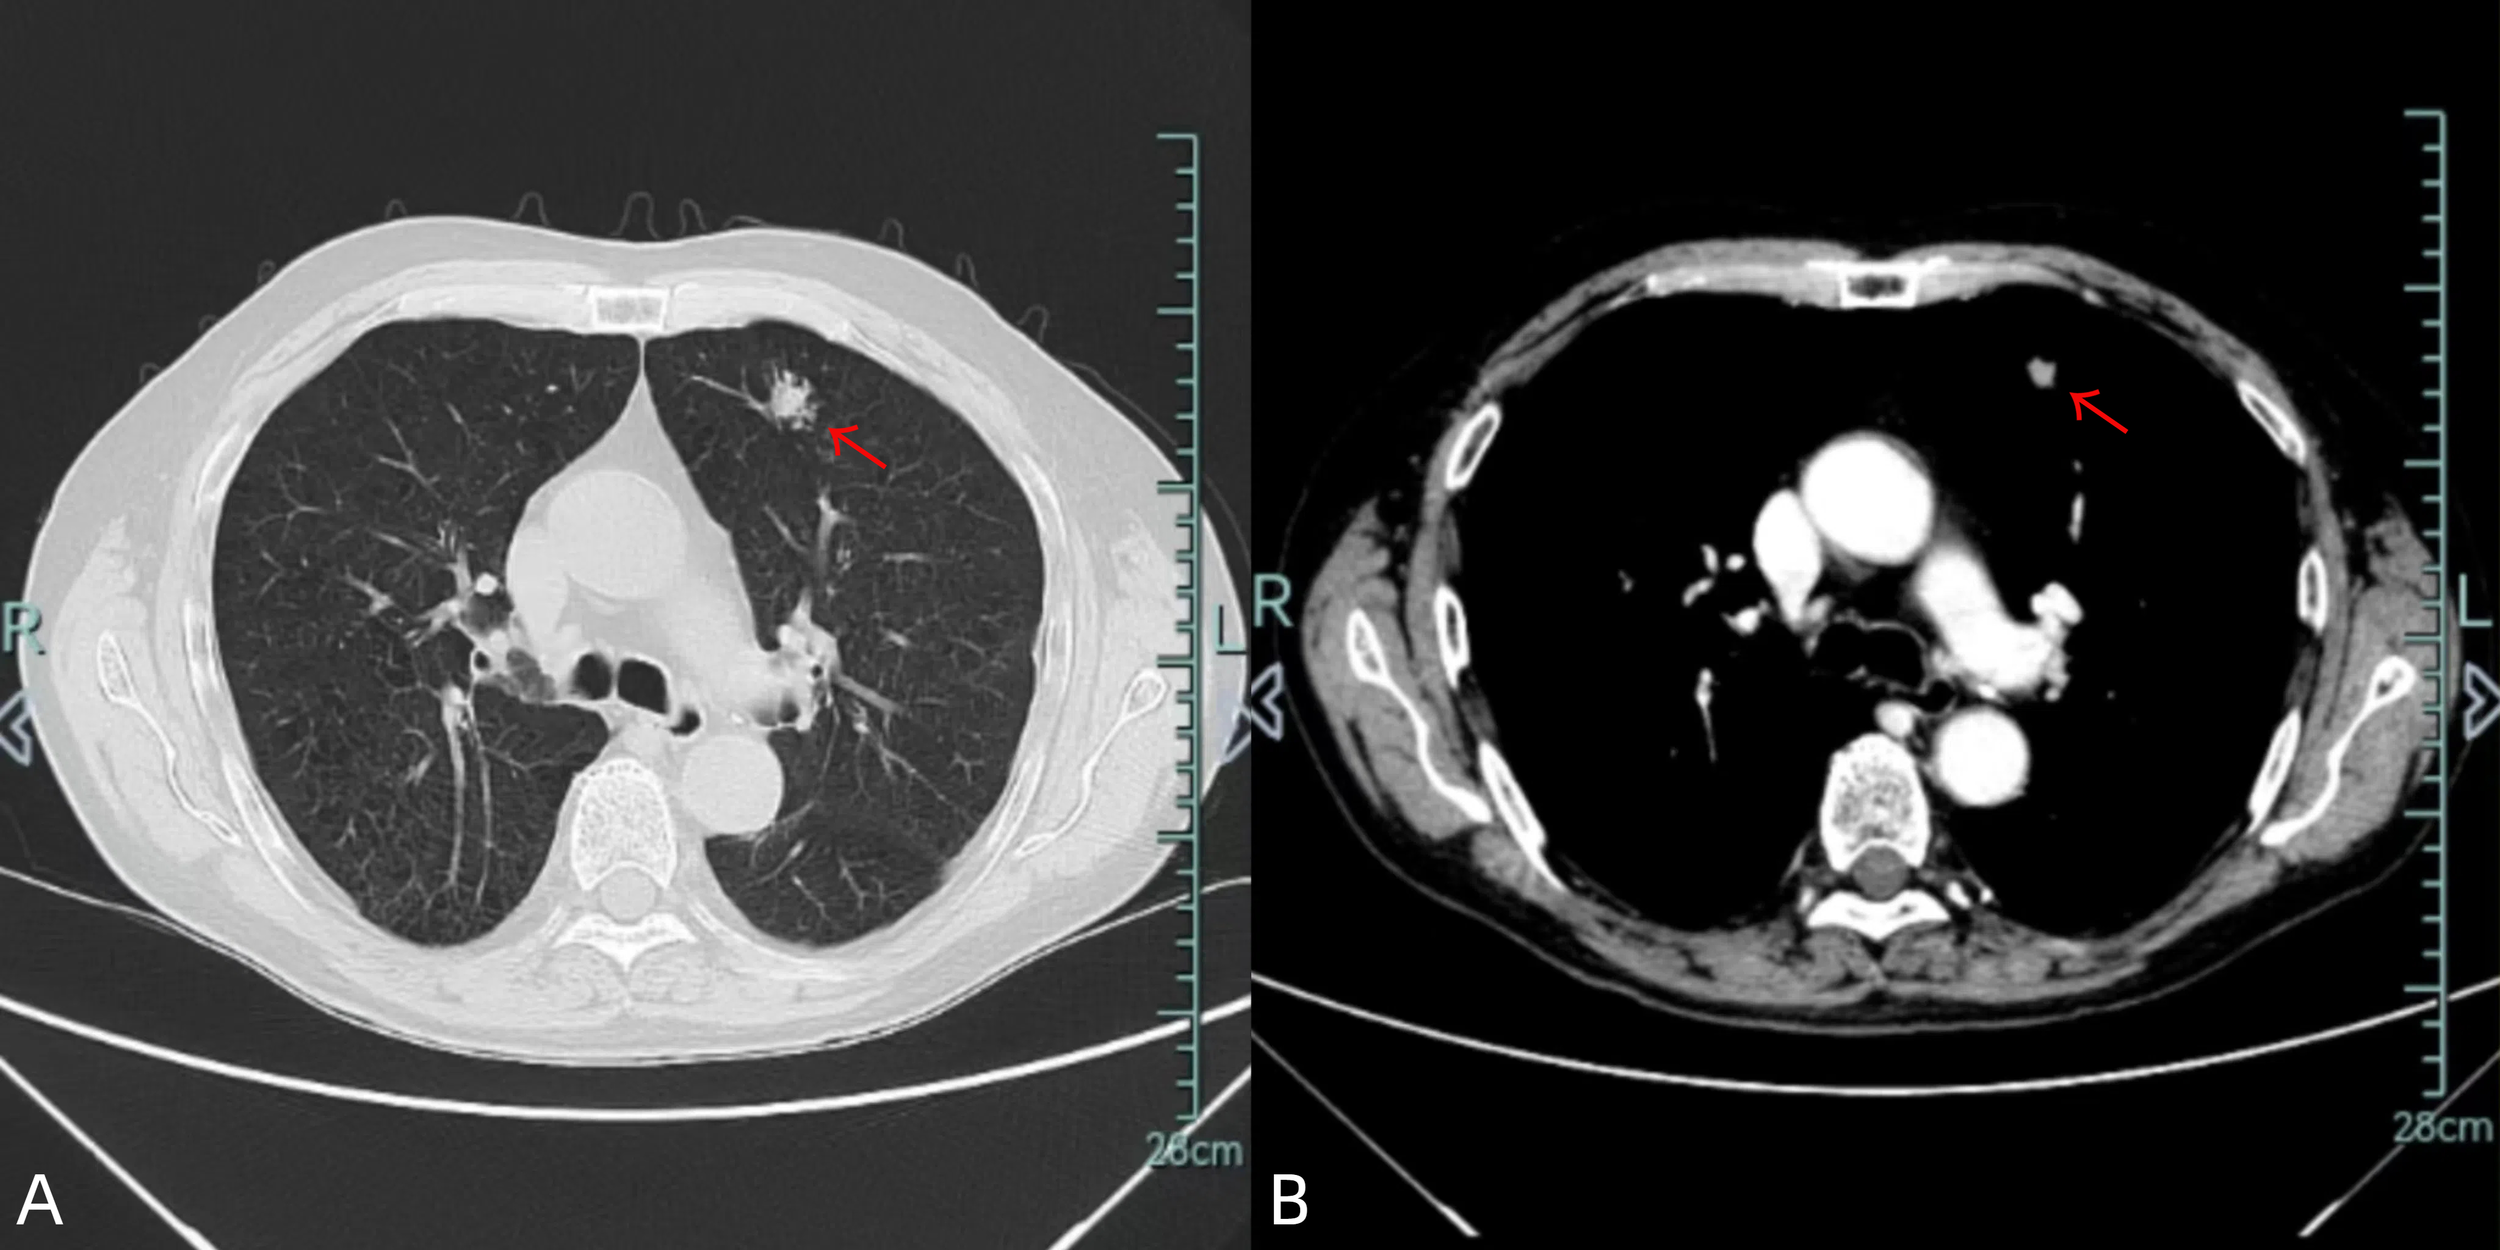

A 70-year-old male ex-smoker (30 pack-years) presented with an incidentally detected 18×11 mm spiculated nodule in the anterior segment of the left upper lobe on chest CT (Figure 1). CT-guided biopsy confirmed adenocarcinoma, prompting further evaluation to exclude metastatic disease. Comprehensive endoscopic evaluation including esophagogastroduodenoscopy and colonoscopy showed no evidence of malignancy or other clinically relevant pathology.

Figure 1

Chest CT images [lung window (A)/mediastinal window (B)] demonstrate an 18×11 mm spiculated nodule in the left upper lobe (red arrow).